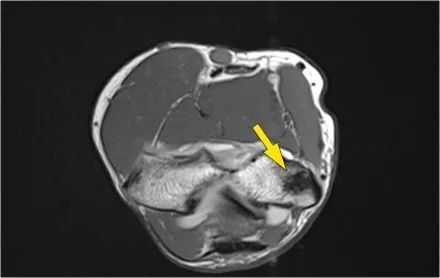

冠状图像上有一个美丽的UCL前束,但注意到关节内侧部分有骨赘形成(红色箭头)。当我们按照顺序向下看,可以看到存在一小部分低信号强度(黄色箭头),这是UCL的一部分撕裂。

这是在X线片可以更好地观察(黄箭头 )。

当我们看轴向扫描时,我们可以欣赏巨大的骨赘形成。请注意,尺骨神经(蓝色箭头)紧邻这些骨赘,这些可能指示尺神经出现病变。